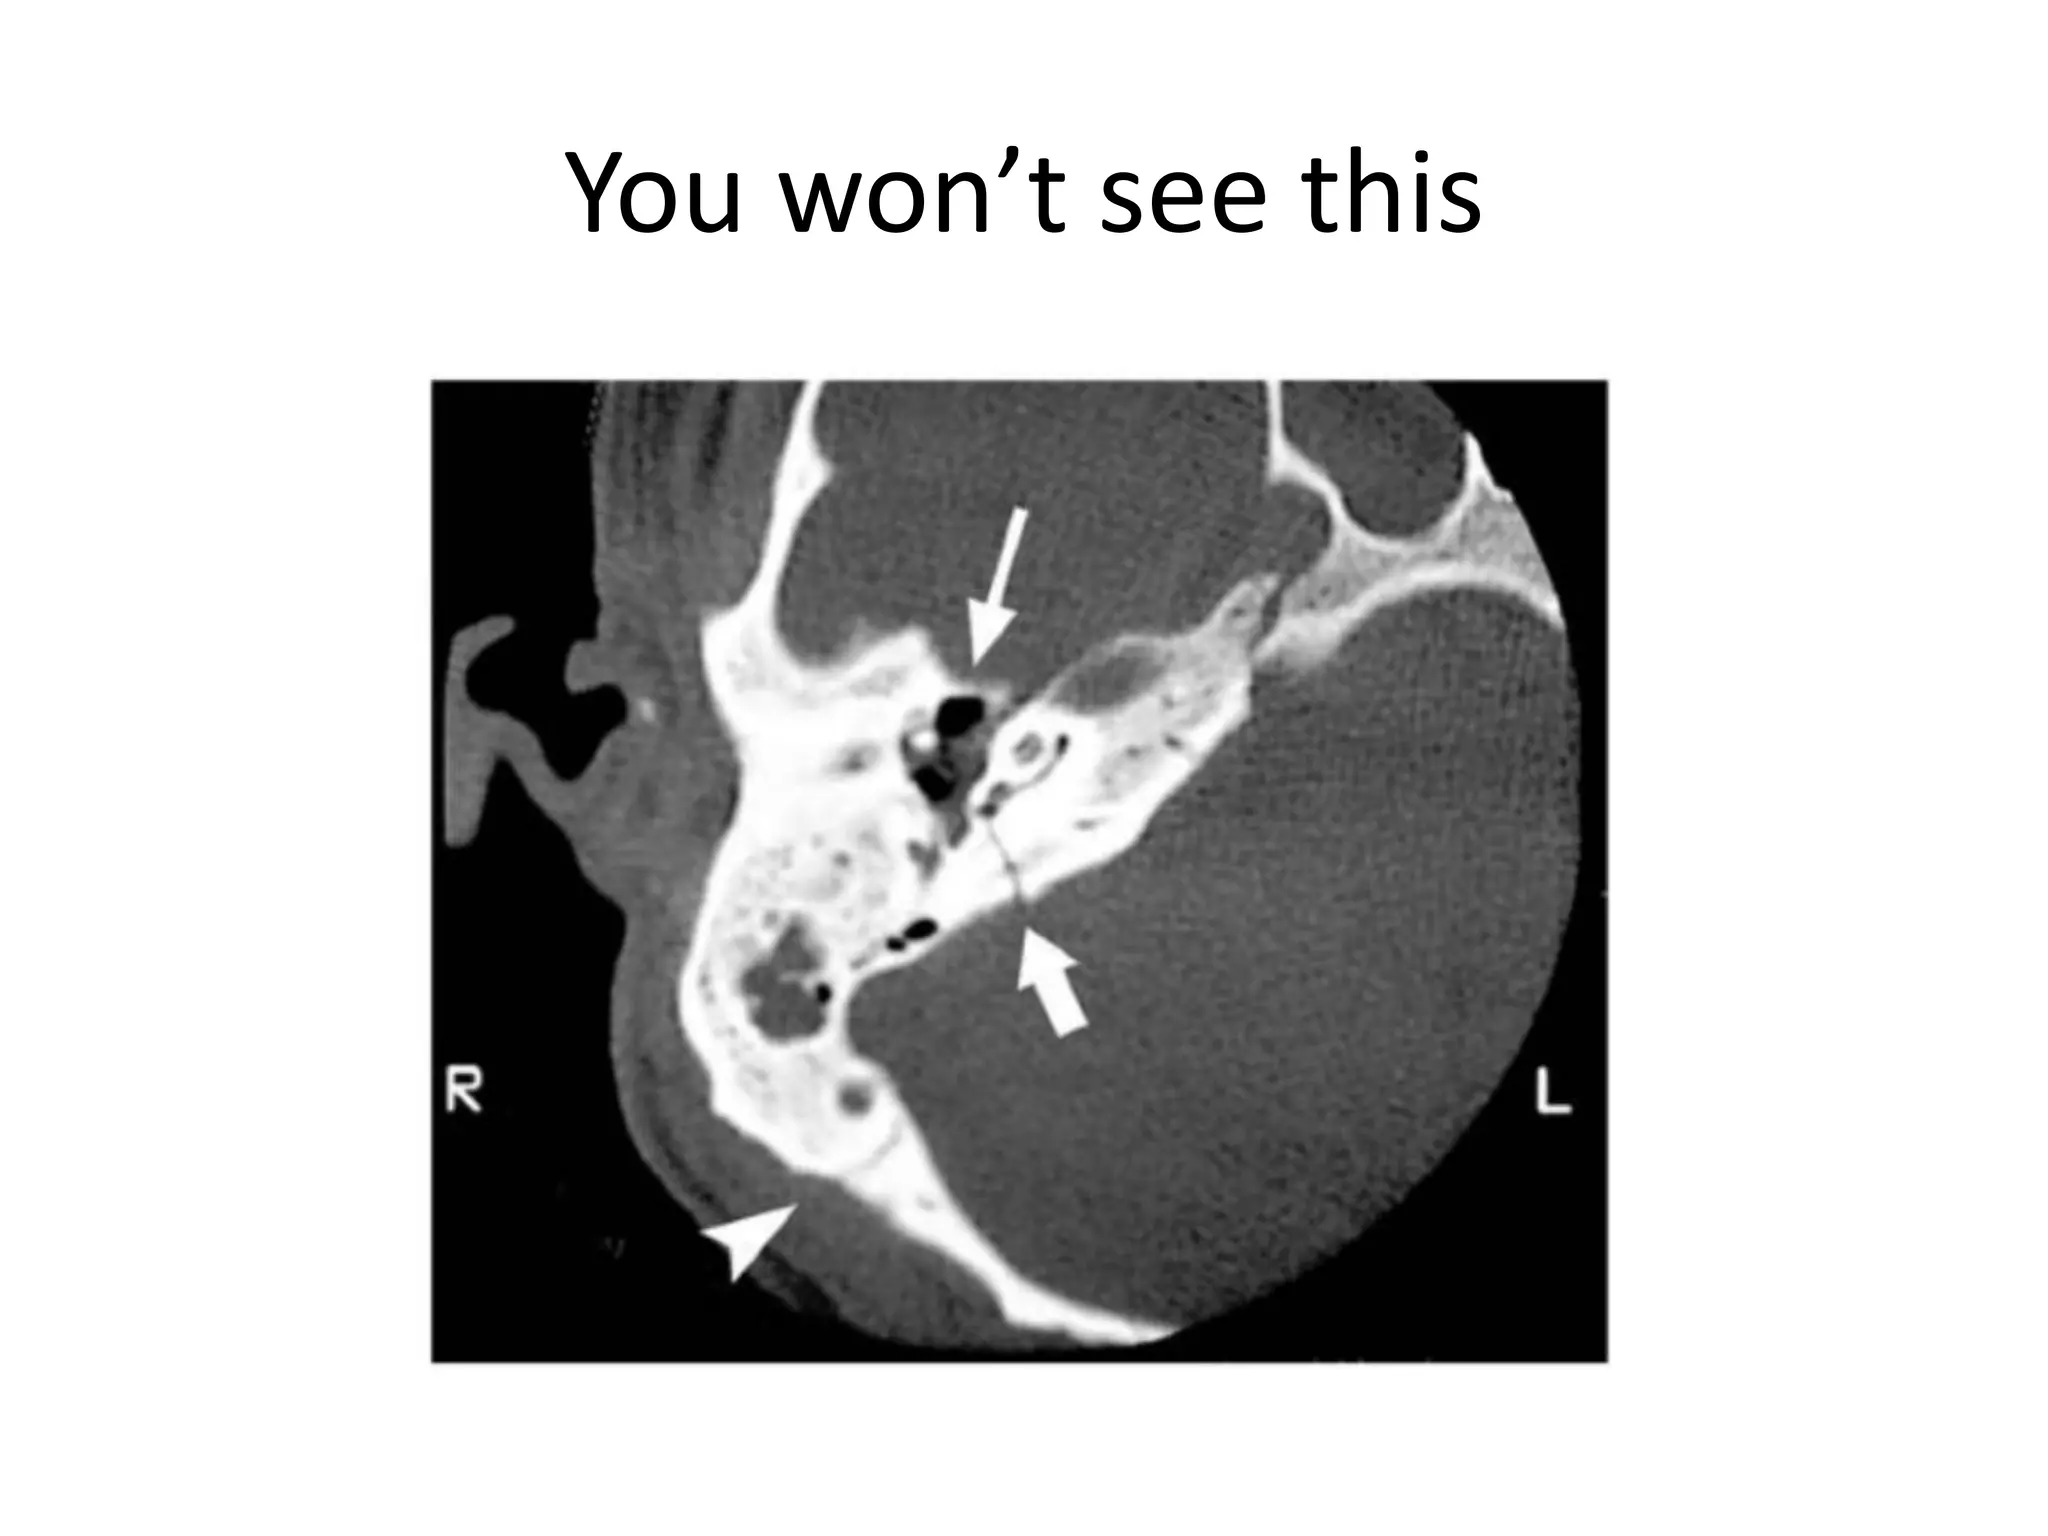

You won’t see this

Bone and Soft TissueIdentify Coup, Contra-coupBasilar Skull FracturePneumocephalus – base or open fxSphenoid Sinus, Ethmoid Sinus, Mastoid Air CellsFacial Trauma

Clinical Signs – Basilar Skull Fracture1234